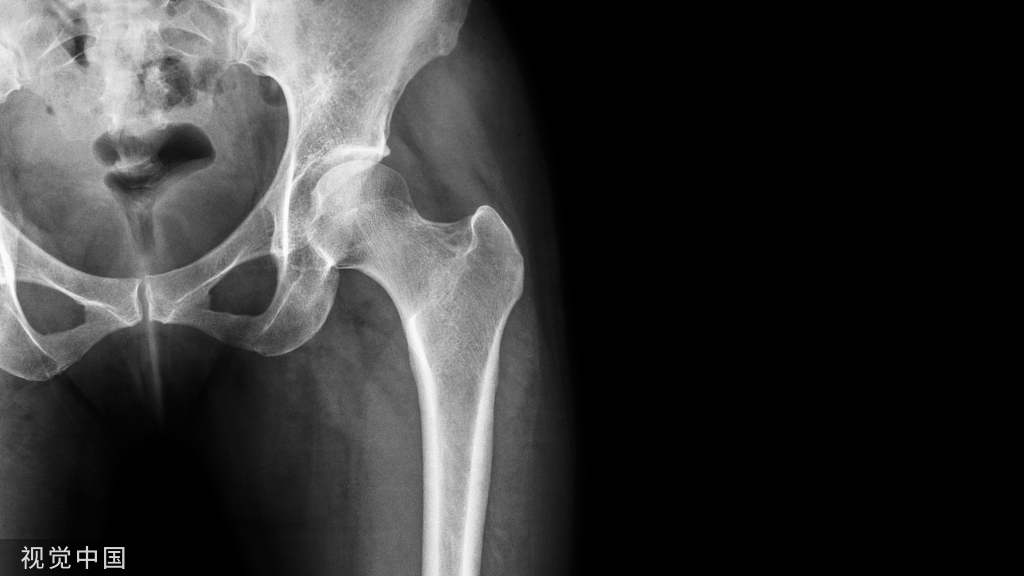

通过腓骨骨折间隙,撑开器撑开,即可暴露后踝骨折及关节面。清理骨折间隙小骨块,复位塌陷的后踝骨折。

经腓骨骨折线撑开显露后踝模式图

手术操作图

该入路虽可显露后踝的骨折间隙,但在清理骨折间隙并复位后,后踝的固定仍需通过第二窗口,即从腓骨长短肌与长屈肌腱之间进入。该方法仅限于显露,协助复位,无法通过该切口固定。